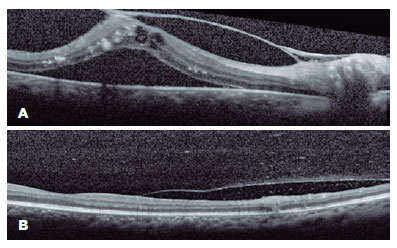

Ancillary tests were performed. Fluorescein angiography showed hyperfluorescence during the early phases followed by leakage, suggesting retinal neovascularization in the OD and early hypofluorescent lesions due to retinal inflammation with delayed staining in the OS (Figure 1). Optical coherence tomography (OCT) revealed tractional retinal detachment in the OD with intraretinal fluid and hard exudates and hyper-reflectivity in the inner retinal layers in the OS (retinitis) with vitreous cells (Figure 2).